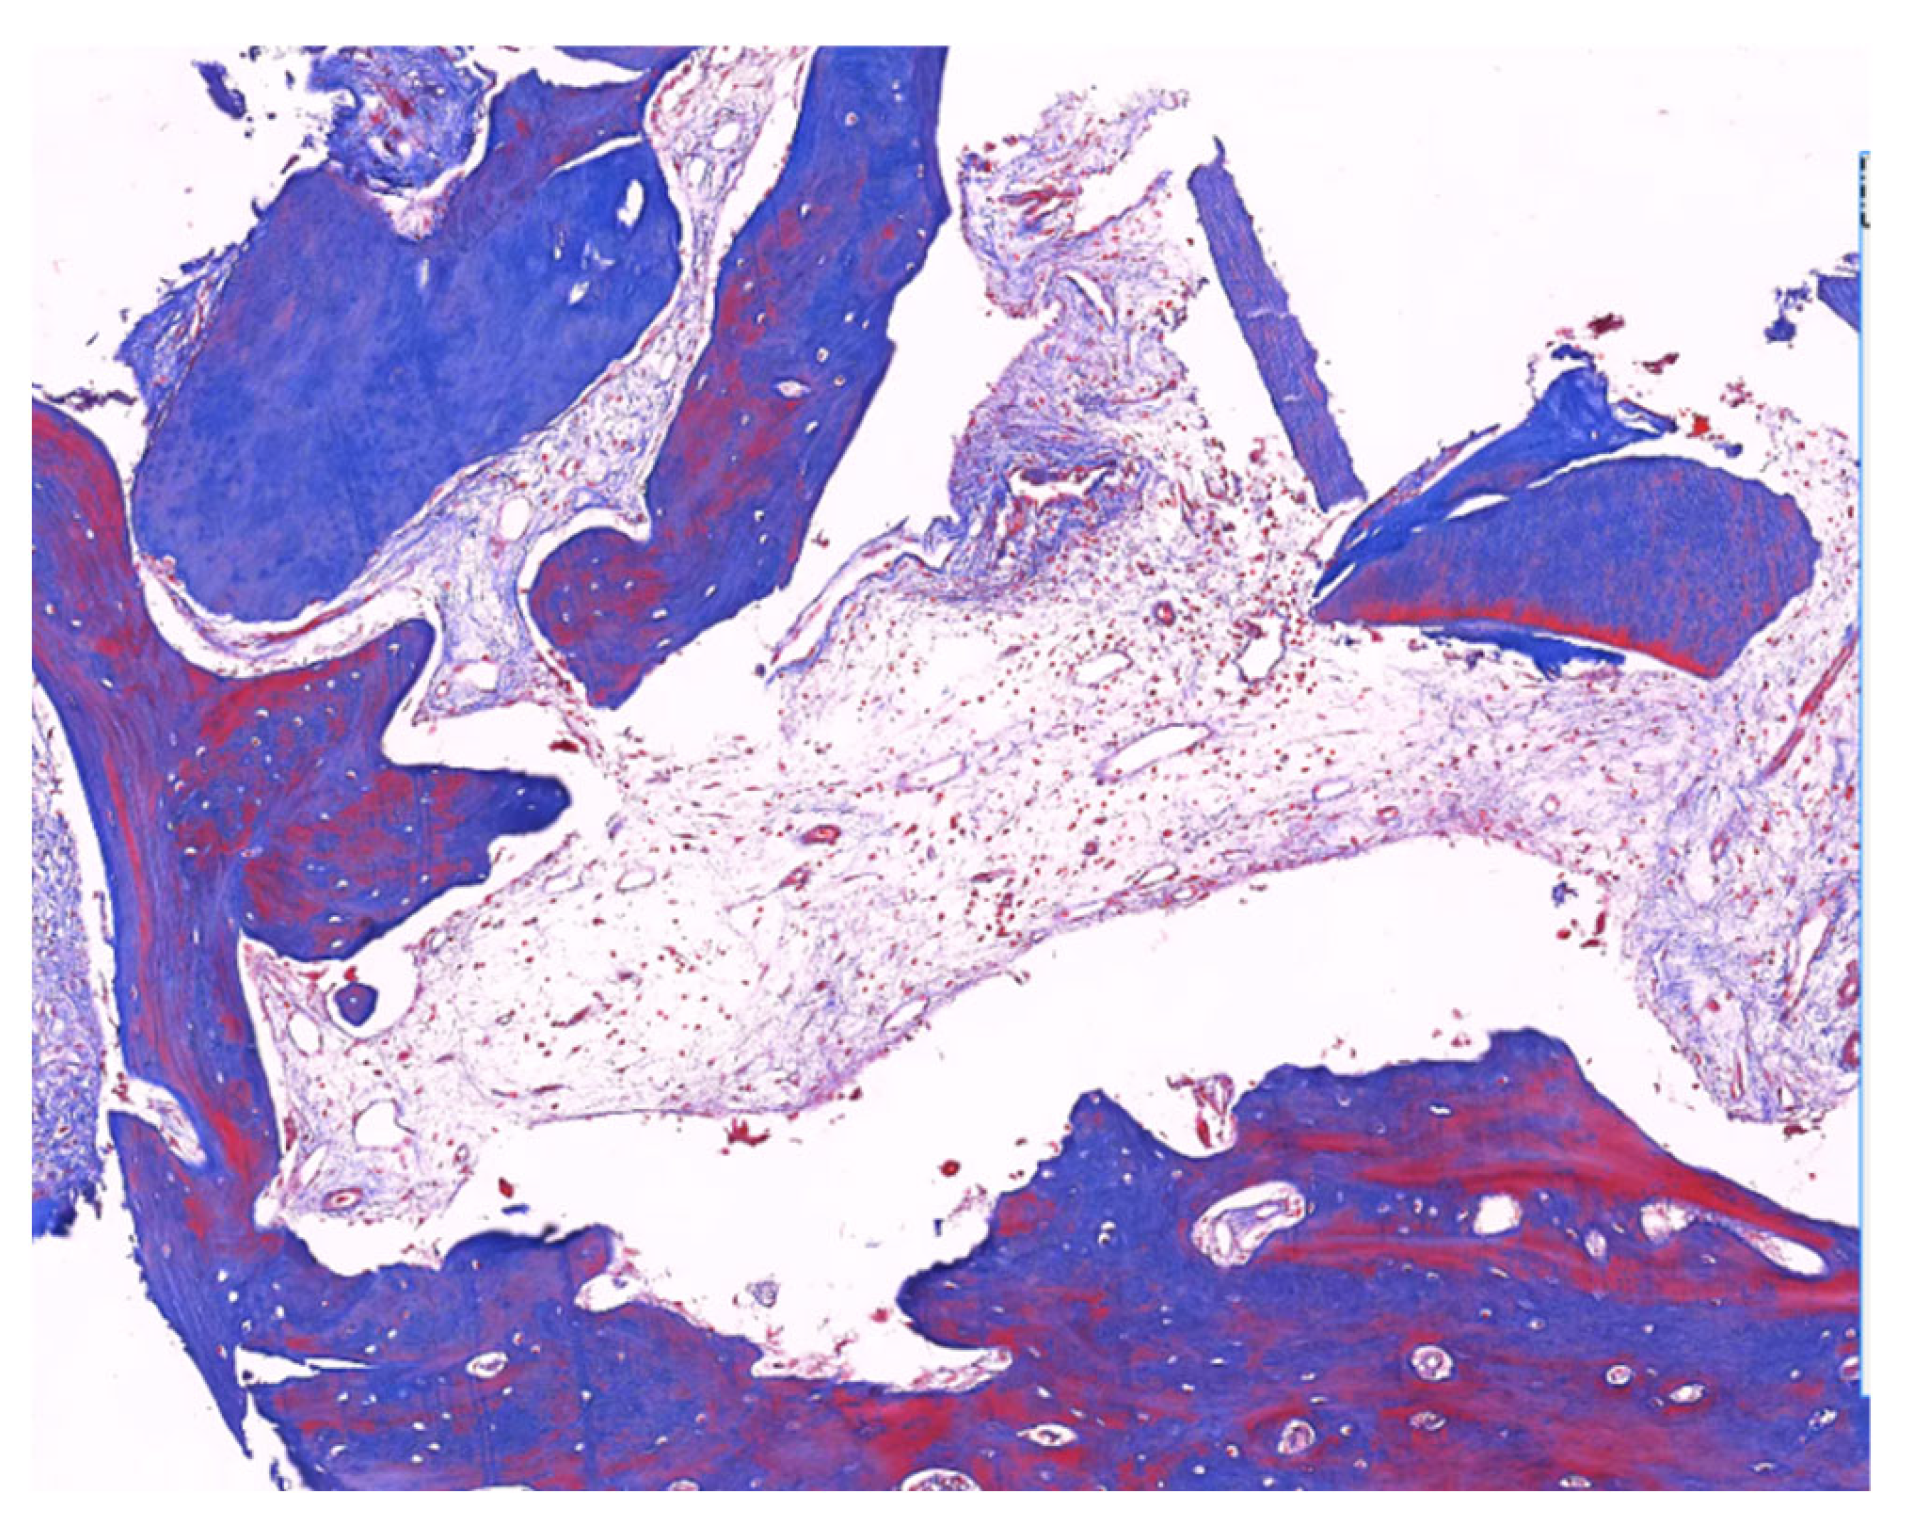

4. Case Report